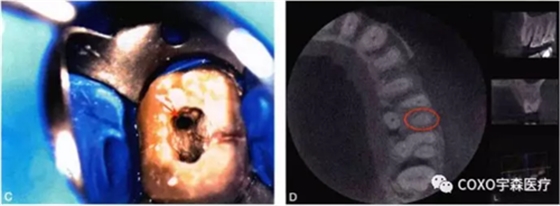

細(xì)小鈣化根管的根管口,即使是在口腔手術(shù)顯微鏡下,也不容易被發(fā)現(xiàn)。在鈣化根管的早期,鈣化牙本質(zhì)的顏色可能與周圍正常牙本質(zhì)不同,因此,多數(shù)情況下,利用口腔手術(shù)顯微鏡能夠發(fā)現(xiàn)根管所在位置。有的鈣化根管牙本質(zhì)與周圍牙本質(zhì)顏色相似,難以區(qū)分,此時(shí)借助手術(shù)顯微鏡的高倍放大作用,結(jié)合根管解剖知識,仔細(xì)觀察顏色的細(xì)微差異,有助于提高探查根管口的成功率。完全鈣化的根管,表現(xiàn)為均質(zhì)的硬組織結(jié)構(gòu),有時(shí)與正常牙本質(zhì)結(jié)構(gòu)難以區(qū)別,當(dāng)采用各種方法均無法疏通時(shí),為了避免產(chǎn)生新的并發(fā)癥,不宜強(qiáng)行疏通,可定期追蹤觀察(圖4-2)